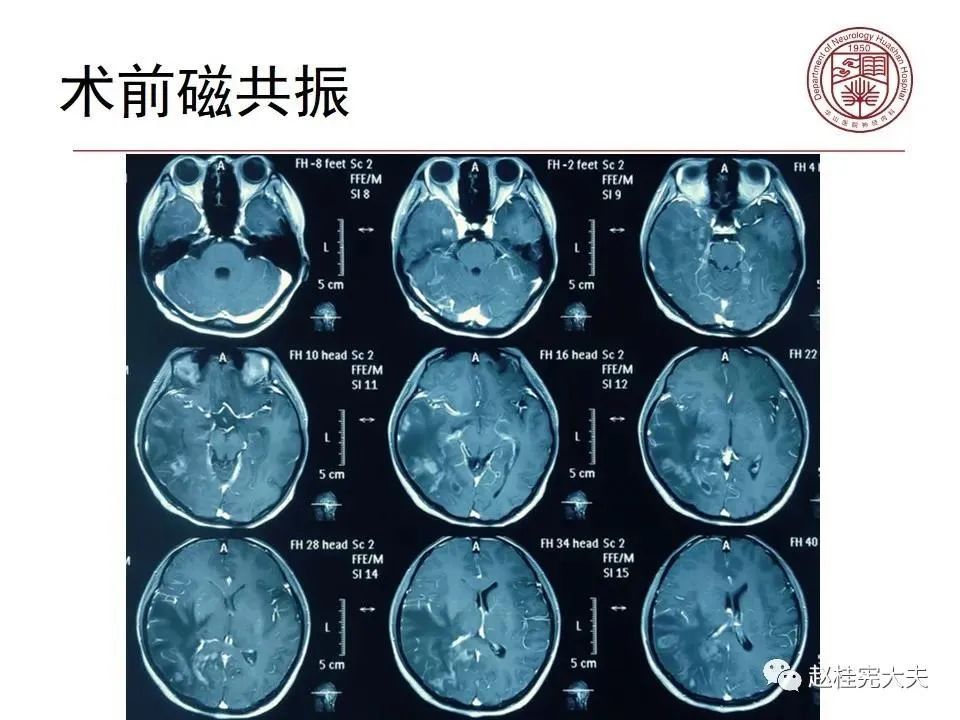

病例3